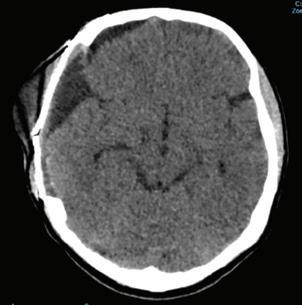

Se hospitaliza del 9 de septiembre de 2022, reali zando TAC de cráneo (Imagen 1) al día 21 del mis mo mes, con diagnóstico de tumor agresivo a nivel frontotemporal derecho realizando resección macro intraoperatoria con bordes sanos. Dura no infiltra da el día 13 de ese mes sin complicaciones. Realizan TAC control (Imagen 2), posteriormente sin residuo tumoral evidente con hematoma extradural, en ese momento se decide manejo médico.

Imagen 2. Postoperatorio. Cambios postquirúrgicos de craniectomía am plia frontoparietal-temporal derecha. Colección residual extraaxial frontal y temporal en el lado derecho, con área de mayor coeficiente de atenua ción en la región temporal, relacionado con hematoma previo conocido.